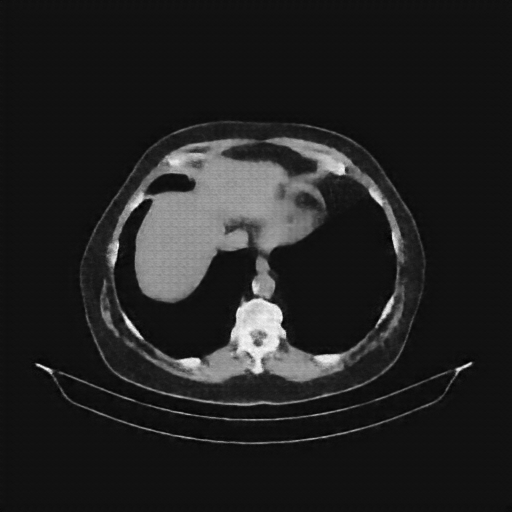

Reconstructed NATIVE CT scan (cycle consistency)

Full window (WL 1023.5, WW 4095 β†’ Low βˆ’1024, High +3071)

Actual HU range: [-863.7, 702.5]